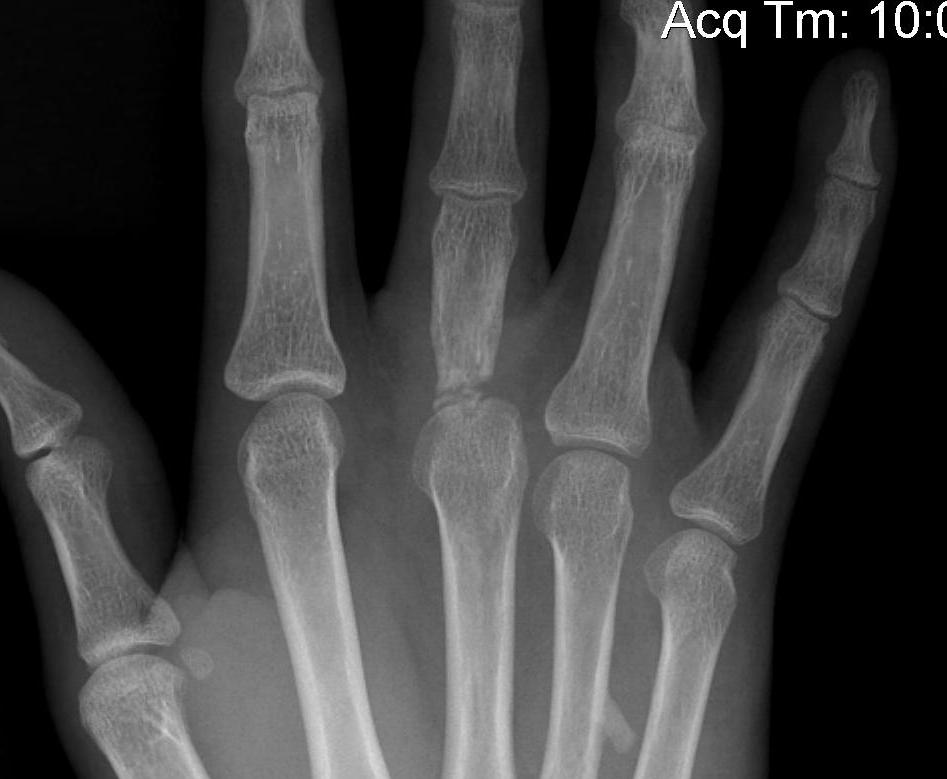

X-rays

3 planes centred on MCPJ middle finger

- AP

- lateral

- oblique

Care to look for subtle evidence joint subluxation